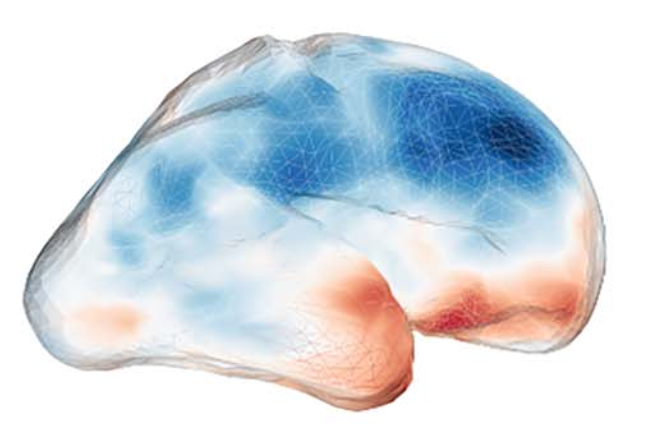

FETALMORPHO

FETALMORPHO - Quantitative Morphometry of Fetal Brain Development for Disease Modeling and Diagnosis, funded by Austrian National Bank Anniversary Fund, (2012 -) We are building a spatio-temporal model - an atlas - of healthy fetal brain development from in utero magnetic resonance imaging (MRI) data from a large group of individuals, and study specific developmental diseases with help of this model.

FETLAS

FETLAS - Assessing Fetal Brain Development Based on a Spatio-Temporal in vivo Atlas Learned from Ultra-Fast Magnetic Resonance Images, funded by a DOC-fFORTE-fellowship of the Austrian Academy of Sciences, (2010 - 2012). This project's goal is to establish a spatio-temporal atlas for the developing human brain during a specific time period. In this context, we will develop methods that synchronously build the atlas as quantitative reference for physicians, as well as performing an automated segmentation of cortical and sub-cortical cerebral structures in fetal Magnetic Resonance Images.

FABRIC

FABRIC - exploring the Formation and Adaptation of the BRaIn Connectome funded by the European Union FP7 - Marie Curie Intra European Fellowships. (2013-2015) The project utilizes in utero fMRI and DTI to explore the emergence of large-scale anatomical pathways that presumably render information exchange channels for the forming of functional activity. Such observations will eventually be integrated into a temporal atlas of the fetal connectome development.